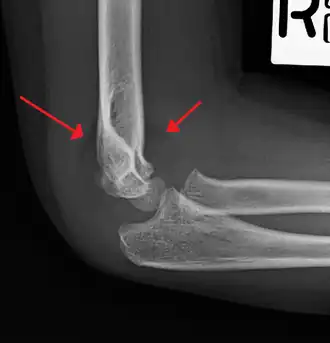

Fish-tail sign - The distal fragment is rotated away from the proximal fragment, thus the sharp ends of the proximal fragment looks like a shape of a fish-tail.[8]

Anterior and posterior sail sign in a child who has a subtle supracondylar fracture -